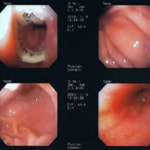

内視鏡下写真

内視鏡検査所見:胃内に竹串の先端部分が残っていたため、異物鉗子にて摘出しました。胃内は、全体的に炎症を伴い、出血している部位も確認されました。摘出後は、胃粘膜保護薬・プロトンプインヒビター(胃薬)の内服2剤ならびに食事療法により経過は良好です。